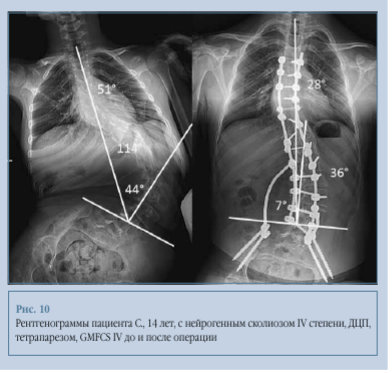

Клинический пример 3. Пациент С., 14 лет, с нейрогенным сколиозом IV степени, ДЦП, тетрапарезом, GMFCS IV. Угол основной сколиотической дуги по Cobb до операции - 114°, после операции - 36°, коррекция - 68,4 %. Перекос таза до операции - 44°, после операции - 7°, коррекция - 84,1 % (рис. 10, 11).